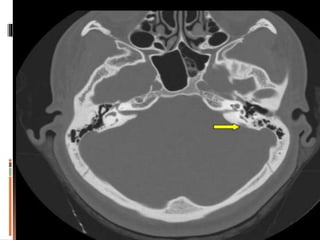

 CT scan (normal aperture 6mm but in meniere 2mm)